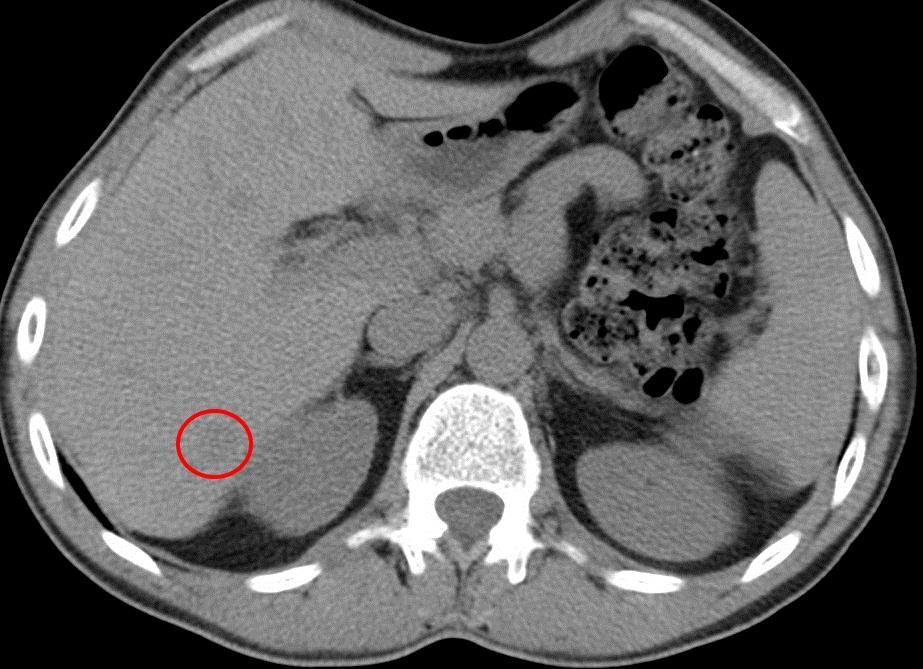

Атипичный мононуклеоз – это инфекционный мононуклеоз, который проявляет себя не характерным образом или протекает в скрытой форме. Диагностика осложняется не типичностью симптоматики. Выявить болезнь достаточно сложно. В этом и заключается опасность – осложнения могут проявить себя внезапно, в то время как человек и не подозревает о заражении.